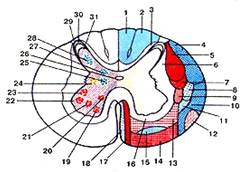

Строение сердца. Общие сведения

Сердце (cor) у человека четырехкамерное. В

сердце расположены продольные перегородки (межпредсердная -4 и межжелудочковая

– 14), которые делят орган на две изолированные половины – правое и левое

сердце, поперечная перегородка делит каждую из этих половин на верхнюю камеру –

предсердие и нижнюю – желудочек сердца.

Строение правого предсердия и желудочка

Правая половина сердца содержит венозную кровь и

состоит из правого предсердия (atrium dexstrum) и правого желудочка

(ventriculus dexter). Правое предсердие имеет форму куба, располагается в

основании сердца справа и позади аорты и легочного ствола. От левого предсердия

отделяется межпредсердной перегородкой (16), на которой находится овальная ямка

(15), которая является остатком овального отверстия через которое сообщаются

между собой предсердия во внутриутробном развитии. В правое предсердие впадает

верхняя полая вена (1), нижняя полая вена (14) и венечный синус (13). Верхняя

часть правого предсердия образована правым ушком сердца (5). Правое предсердие

сообщается с правым желудочком при помощи предсердно-желудочкового отверстия.

Правый желудочек имеет форму треугольной

пирамиды, с верхушкой обращенной вниз и располагается справа и спереди от

левого желудочка. От левого желудочка отделяется при помощи межжелудочковой

перегородки. Вверху в стенке желудочка есть два отверстия: сзади – правое

предсердно-желудочковое, а спереди – отверстие легочного ствола.

Предсердно-желудочковое отверстие закрывается при помощи трехстворчатого

клапана (8). Внутри правого желудочка находятся трабекулы и сосочковые мышцы,

от которых к створкам клапана идут сухожильные хорды. Из правого желудочка

начинается легочной ствол (6). Между правым желудочком и легочным стволом

находится полулунный клапан легочного ствола.

Строение левого предсердия и желудочка

Левая половина сердца содержит артериальную

кровь и состоит из левого предсердия (atrium sinistrum) и левого желудочка

(ventriculus sinister).

Левое предсердие имеет форму неправильного куба,

отграничено от правого межпредсердной перегородкой, имеет левое ушко (15). В

левое предсердие открываются 4 легочные вены, лишенные клапанов, они приносят

артериальную кровь от дёгких. С левым желудочком сообщается с помощью

предсердно-желудочкового отверстия, возле которого находятся гребенчатые мышцы.

Левый желудочек (16) конусовидный, его основание

обращено кверху. В переднем верхнем отделе желудочек сообщается с аортой. У

места выхода аорты из левого желудочка имеется клапан аорты, который состоит из

правой, левой и задней полулунных заслонок. В предсердно-желудочковом отверстии

располагается двухстворчатый клапан (митральный – 7).

На внутренней поверхности левого желудочка

находятся мясистые трабекулы (10) и две сосочковые мышцы (9), от которых идут

сухожильные хорды (8), прикрепляющиеся к свободным краям створок митрального

клапана.

Толщина стенок левого предсердия около 2 мм, а

желудочка – до 15 мм. Верхушку сердца полностью выполняет левый желудочек.